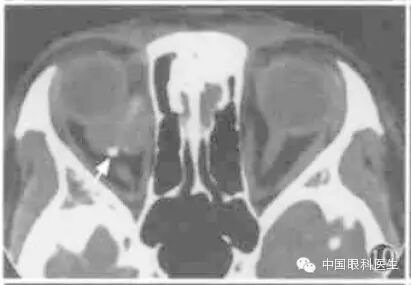

眶内静脉曲张常规CT扫描时多不显影,或仅显示小部分病变,欲观察病变全部范围可行颈部加压检查(图1,图2)。将血压计袋缠于患者颈部,摆好位置,加压至5.33kPa(高于静脉压),再行扫描检查,扫描完毕后立即将气囊放松。

图1左眶静脉曲张,平扫CT显示左眶后少许软组织密度(箭头)

图2同例静脉曲张加压后CT显示左眼球明显出土,球后出现巨大高密度软组织块影(箭头)